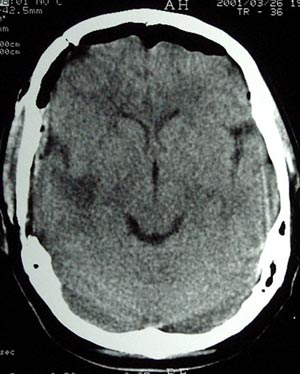

Figura 63 - Ressonância nuclear magnética pós-operatória mostrando adequada ressecção da lesão. Esse paciente ficou livre de crises.